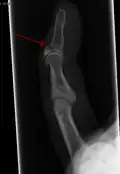

Un doigt en maillet résulte généralement d'une hyperflexion de la phalange distale[1]. Cela se produit généralement lorsqu'un ballon percute un doigt tendu et le bloque. Il en résulte soit une lésion du tendon soit un arrachement osseux par le tendon qui reste intacte. Le diagnostic est généralement basé sur les symptômes et confirmé par des radiographies.

Le diagnostic est généralement basé sur les symptômes et confirmé par des radiographies[1]. La lésion peut être accompagnée d'un œdème et d'une ecchymose[3].